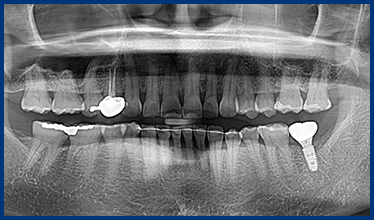

CASE 01

• 치료 전

• 발치 후 임플란트 즉시 식립

• 임플란트 보철 후